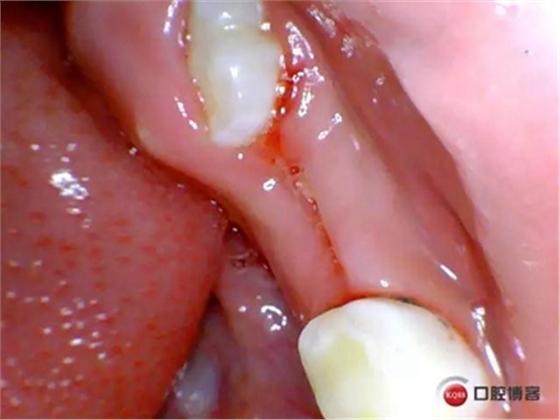

處理:*75局麻下拔除,壓迫止血,不適隨診。